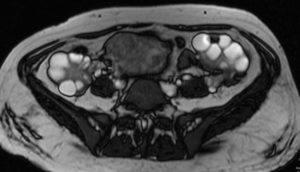

МРТ яичников. Визуализируются множественные кисты обоих яичников

МРТ яичника. У женщин с её слов был дискомфорт в малом тазу. Выявляется образование правого яичника. С множественными перегородками свидетельствуют о множественном количестве кист. Так кисты имеют гиперинтенсивный сигнал на Т2 то мы можем сказать о серозном содержимым в кистах. Диагноз: серозная цистаденофиброма яичника.